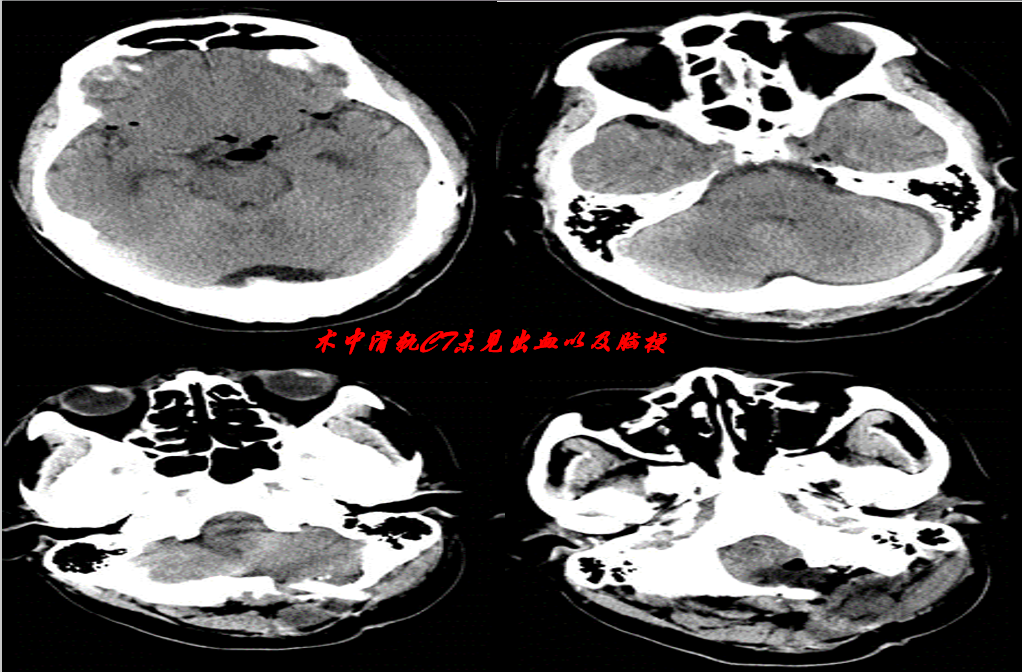

术中滑轨CT未见出血以及脑梗